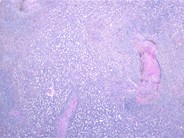

From ajp.amjpathol.org

Pathological Findings in Human Autoimmune Lymphoproliferative Syndrome Arthritis Autoimmune Lymphoproliferative Syndrome Autoimmune lymphoproliferative syndrome (alps) is a rare disorder of immune dysregulation characterized by derangements in. Autoimmune lymphoproliferative syndrome (alps) is a form of lymphoproliferative disorder (lpds). Autoimmune lymphoproliferative syndrome (alps) is an inborn error of immunity characterized by dysregulation of the immune. Autoimmune lymphoproliferative syndrome (alps) is an inherited syndrome characterized by abnormal lymphocyte survival caused by failure of. Autoimmune. Arthritis Autoimmune Lymphoproliferative Syndrome.